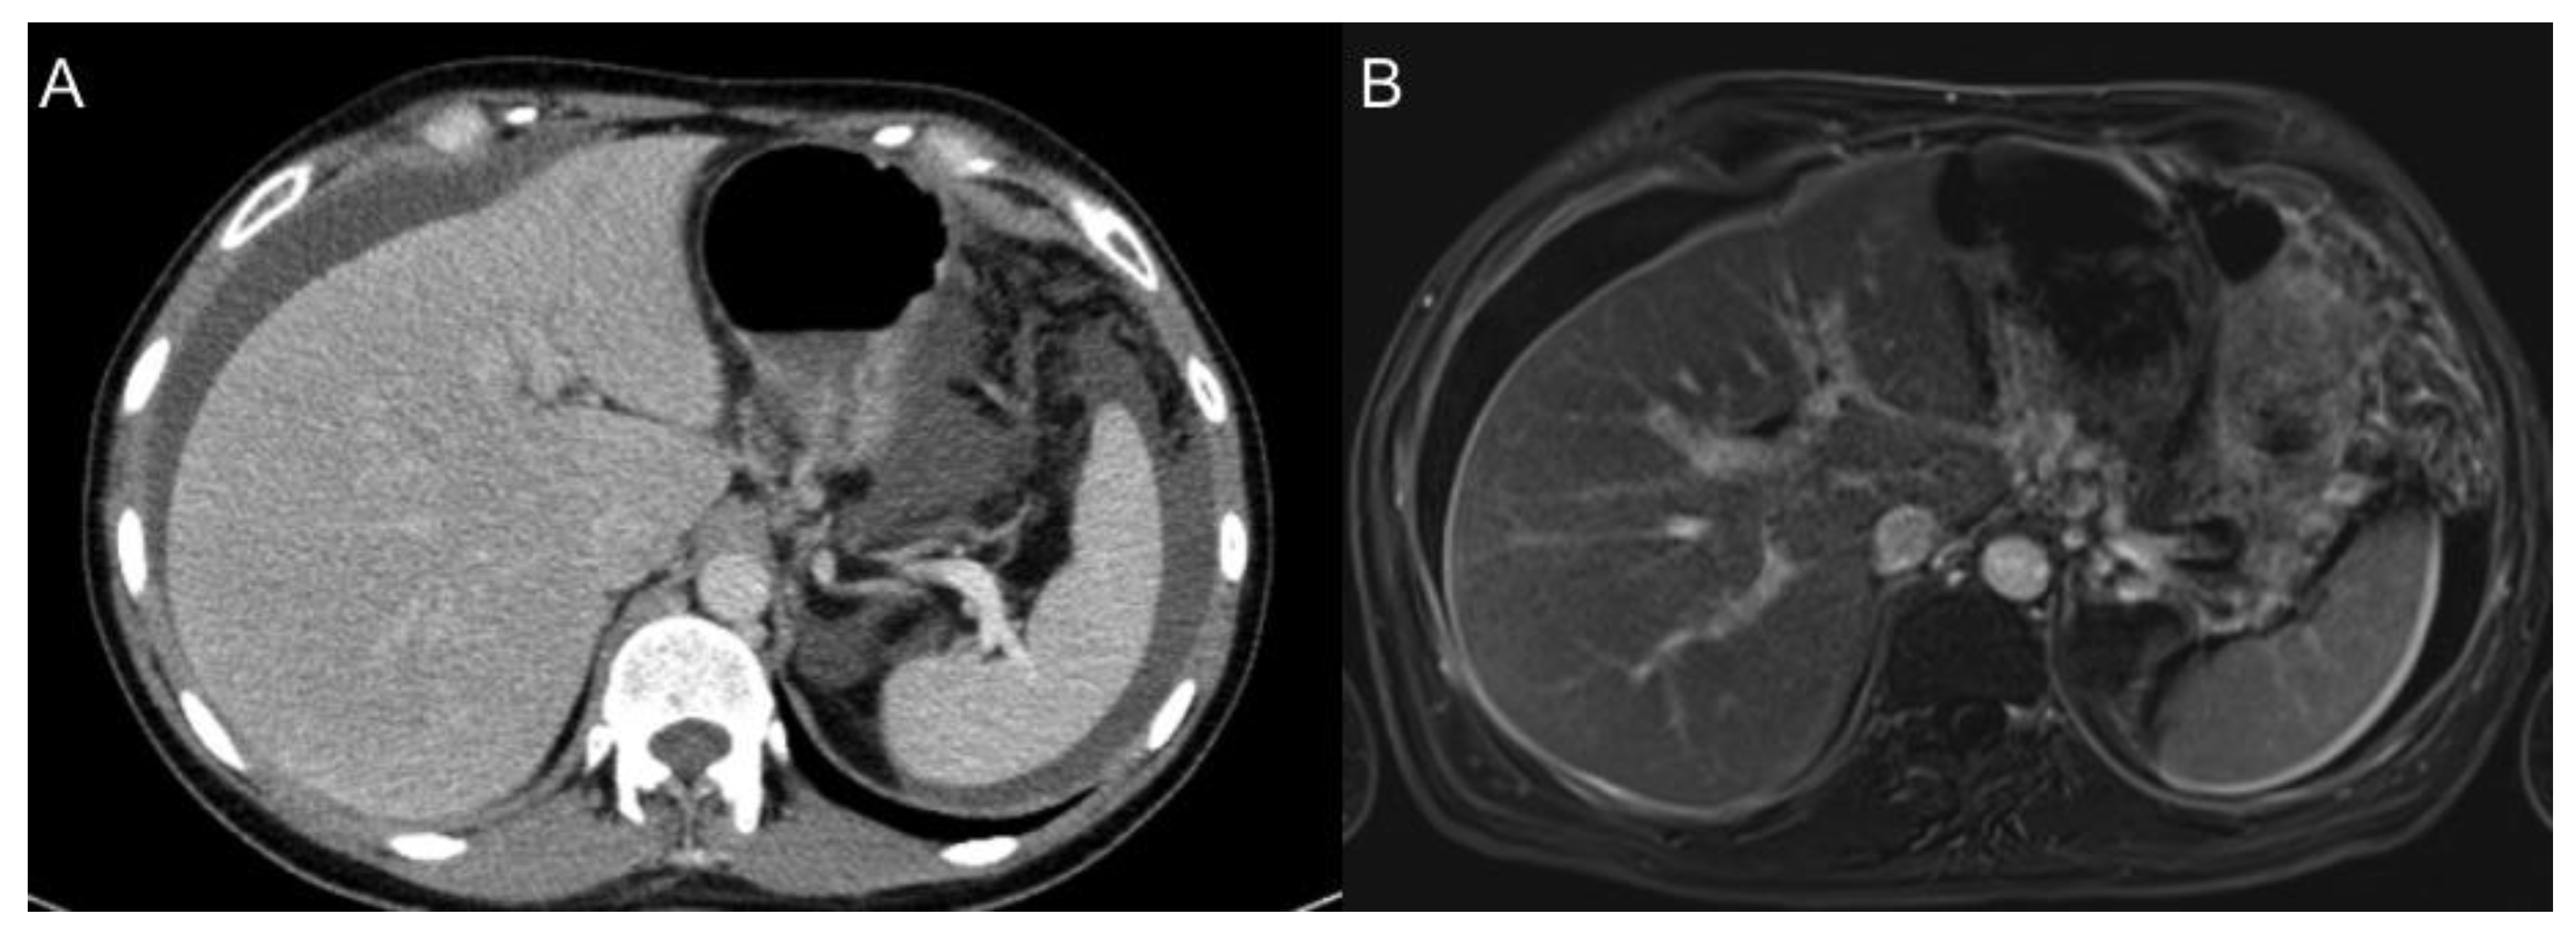

- Kim, S.H.; Choi, Y.H.; Kim, J.W.; Oh, S.; Lee, S.; Kim, B.G.; Lee, K.L. Clinical significance of computed tomography-detected ascites in gastric cancer patients with peritoneal metastases. Medicine 2018, 97, e9343. [Google Scholar] [CrossRef] [PubMed]